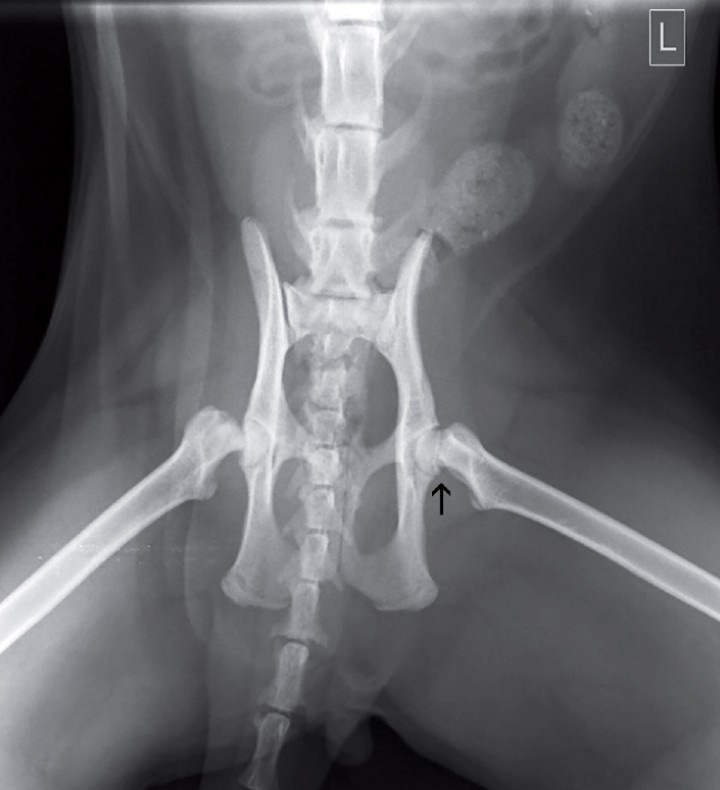

A veces, la proyección ventrodorsal con los miembros en extensión de la cadera no muestra anormalidades evidenciables de desplazamiento de la epífisis femoral proximal, porque la extensión de las extremidades provoca tensión en las fibras de colágeno de la cápsula articular manteniendo reducida la fractura o el desplazamiento epifisario e impidiendo su visualización. Sin embargo, la proyección ventrodorsal con las extremidades libremente en abducción o posicionamiento en rana (Fig. 3), permitió la observación del desplazamiento entre la epífisis proximal femoral derecha y la metáfisis, así como la mala congruencia entre el cuello femoral y la epífisis proximal izquierda. No obstante, el diagnóstico definitivo no se alcanzó únicamente con el examen radiográfico.

<p>Proyección ventrodorsal con las extremidades en abducción. Se observa un desplazamiento entre la epífisis proximal femoral derecha y la metáfisis, así como la mala congruencia entre el cuello femoral y la epífisis proximal izquierda (flecha). L: izquierda.</p>

Figura 3

Proyección ventrodorsal con las extremidades en abducción. Se observa un desplazamiento entre la epífisis proximal femoral derecha y la metáfisis, así como la mala congruencia entre el cuello femoral y la epífisis proximal izquierda (flecha). L: izquierda.